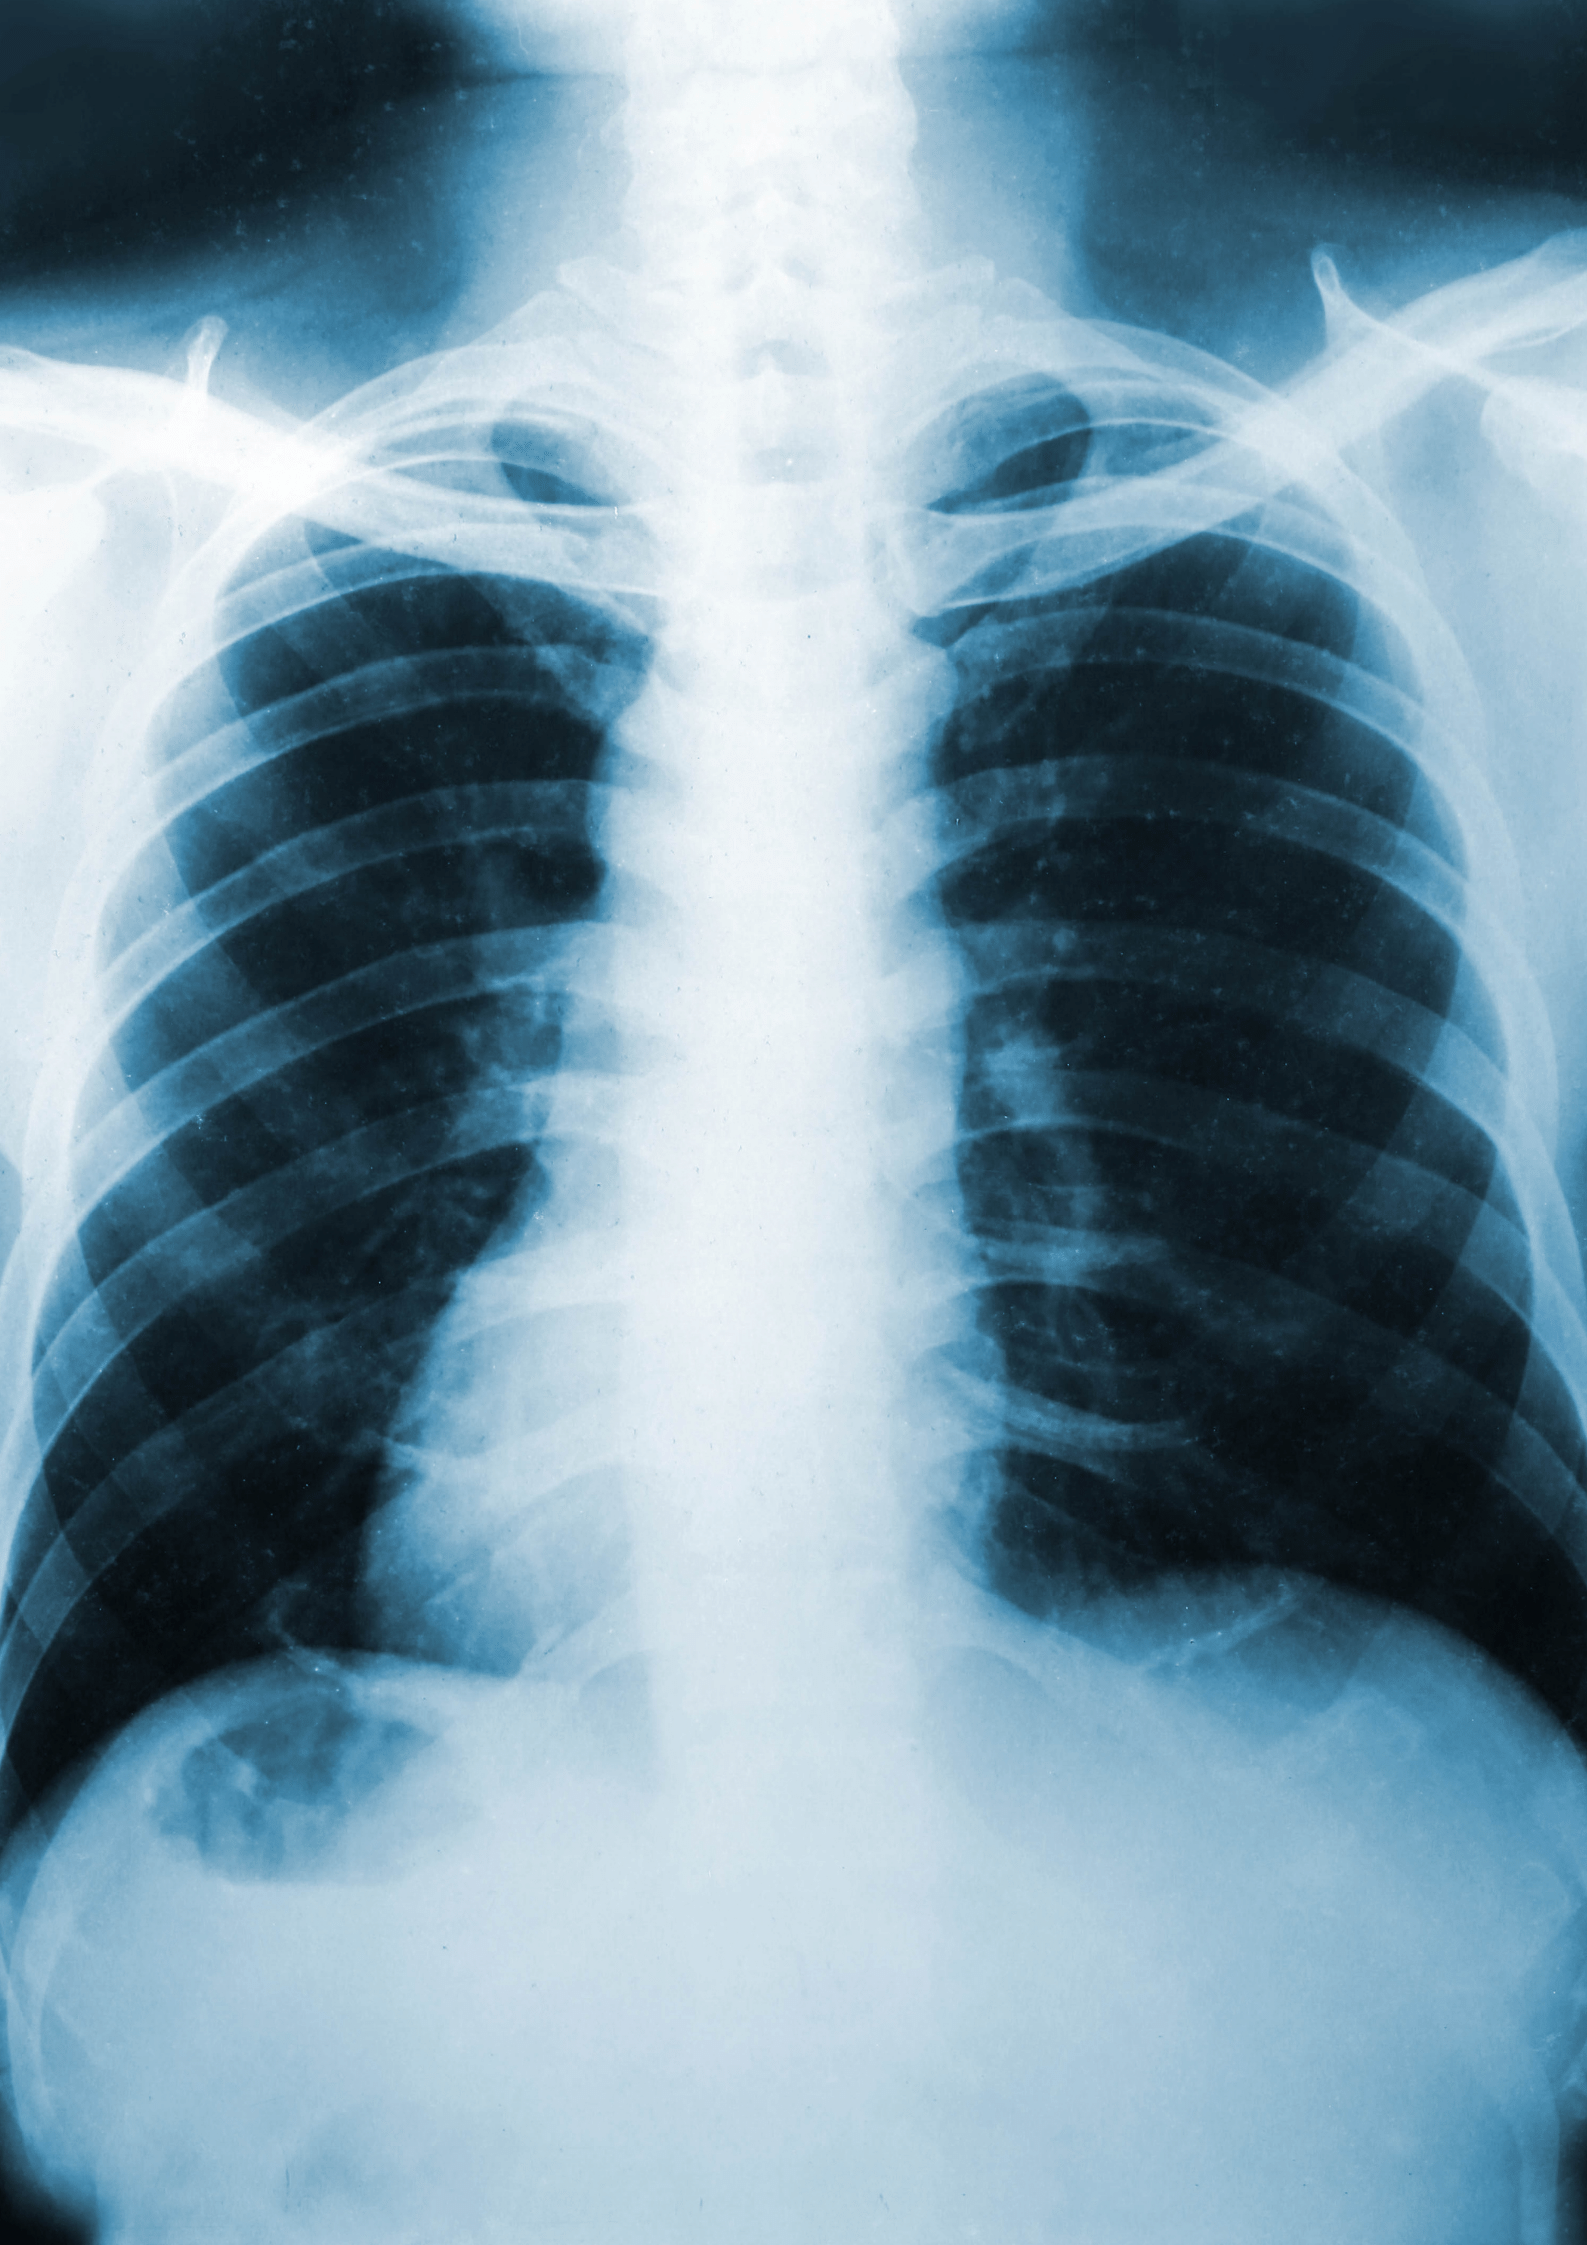

A variety of imaging techniques are used to diagnose or treat diseases. Radiology is divided into two different areas, Diagnostic Radiology and Interventional Radiology .

Diagnostic Radiology (DR) refers to the field of medicine that uses non-invasive imaging scans to diagnose a patient. The tests and equipment used sometimes involves low doses of radiation to create highly detailed images of an area.